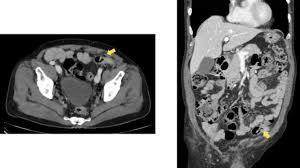

Pdf An Unusual Case Of A Strangulated Right Inguinal Hernia Containing The Sigmoid Colon from i1.rgstatic.net Shelby is very active on our site always there to help others along their way, offering support and answering questions that those who are just starting. It may lead to immediate death, so you have to know symptoms and early warning signs of colon cancer to protect yourself against this disaster. An inguinal hernia containing colorectal cancer is rare but serious and can often present with complications such as perforation. In this condition, pain is caused on the left side of the abdomen but it can also be at the right side, which is quite close to the location of the appendix. Because hernias are more common in men than in women, they can sometimes be an overlooked source of pain for women, according to the society of laparoendoscopic surgeons (sls). A hernia happens anytime a body part pushes into a place where it doesn't belong. A tumor is a solid or cystic mass. The use of synthetic mesh in association with colonic resection did not lead to post operative infection, allowing concomitant treatment of both diseases in elderly, high risk patients.

We therefore conclude that the association between colon cancer and inguinal hernia is mainly coincidental, and the cancer must be suspected on a clinical basis. Less than 1 out of 200 cases of crc is localized within an inguinal hernia 6 . It may lead to immediate death, so you have to know symptoms and early warning signs of colon cancer to protect yourself against this disaster. Colon cancer is a very critical issue and maybe one of the causes of sudden death in young men, women and elderly. I performed an scope examination of her esophagus and confronted a huge cancer occupying the lower portion of her esophagus. The use of synthetic mesh in association with colonic resection did not lead to post operative infection, allowing concomitant treatment of both diseases in elderly, high risk patients. In the region of the inguinal canal, where most hernias occur, there are lymph nodes that can enlarge from infectious or malignancies, and can be mistaken for a hernia. When a hernia meets cancer. A tumor is a solid or cystic mass. A female patient came to see me with some difficulty swallowing, a very routine issue for a gastroenterologist. When colon cancer is detected in its early stages, there may be no symptoms present at all. Typically, patients with ventral hernias describe mild pain, aching or a pressure sensation at the site of the hernia. As detailed in the risk factors, acid reflux caused by hiatal hernia is one of the main cause of esophageal cancer.

From Inguinal Hernias To Spermatic Cord Lipomas Pearls Pitfalls And Mimics Of Abdominal And Pelvic Hernias Radiographics from pubs.rsna.org The discomfort worsens with any activity that puts a strain on the abdomen, such as heavy lifting, running. Cancer misdiagnosis can have devastating results for the patient. It may lead to immediate death, so you have to know symptoms and early warning signs of colon cancer to protect yourself against this disaster. Colon cancer may be diagnosed with the following colon cancer testing: A hernia happens anytime a body part pushes into a place where it doesn't belong. Symptoms of hiatal hernia include: Typically, patients with ventral hernias describe mild pain, aching or a pressure sensation at the site of the hernia. In the region of the inguinal canal, where most hernias occur, there are lymph nodes that can enlarge from infectious or malignancies, and can be mistaken for a hernia.

Although still considered rare, adenocarcinoma of the esophagus, the most common form of esophageal cancer, is one of the. Since a hiatal hernia often exhibits the same symptoms as other conditions, it can be easily mistaken for something else entirely. De caestecker discusses hernia symptoms and what they might be mistaken for. Initial common symptoms in patients presenting with colon cancer are abdominal pain, change in bowel habits, melaena, and general weakness 5 . Colonoscopy, a procedure which involves a flexible tube with an attached video camera. Some of the other medical conditions that can be confused with appendicitis include: In cases where cancer is not identified or mistaken for another disease, patients may miss a critical window for treatment. As detailed in the risk factors, acid reflux caused by hiatal hernia is one of the main cause of esophageal cancer. Many conditions can cause hip pain, and cancer is one of them. An inguinal hernia containing colorectal cancer is rare but serious and can often present with complications such as perforation. Less than 1 out of 200 cases of crc is localized within an inguinal hernia 6 . Do not hesitate to consult your cancer doctor immediately and visit a colon cancer center if you suffer from any of these warning signs. She is an endometrial cancer survivor and is starting to get compfortable with the idea of being a survivor.